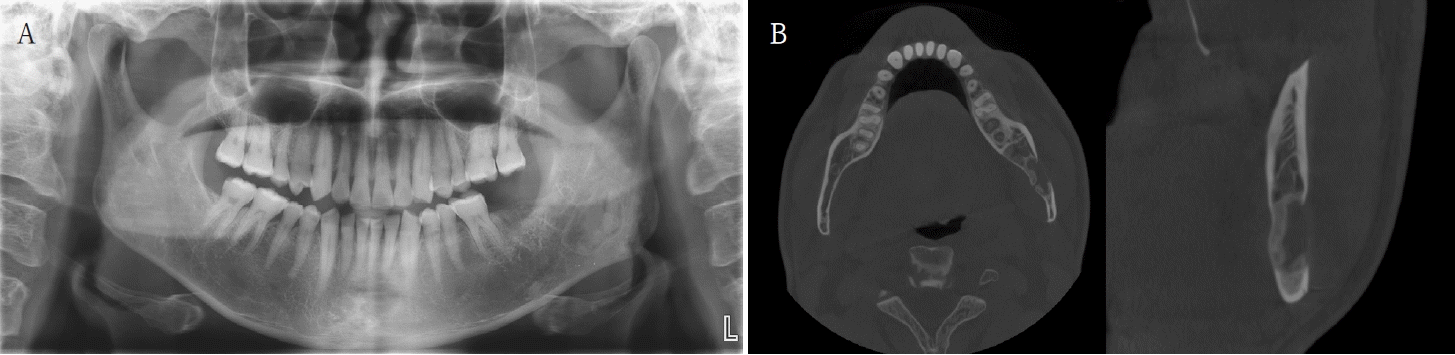

Fig. 4.

A. Panoramic radiograph at 7 months postoperatively shows new bone formation along the superior and inferior aspects of the postoperative defect, without recurrence. B. Cone-beam computed tomographic images at 7 months shows new bone formation along the superior, inferior, and lingual aspects of the postoperative defect.

A 52-year-old male was referred to the Gangneung-Wonju National University Dental Hospital, from a local dental clinic for evaluation of a lesion in the left mandibular angle and ramus. The lesion had been identified on a panoramic image obtained for the extraction of the left mandibular second molar, five days prior to presenting to our hospital. Clinical examination, including both intraoral and extraoral assessments, revealed no remarkable findings.The patient underwent a panoramic radiograph and cone-beam computed tomography (CBCT). The panoramic radiograph showed an ovoid, well-demarcated radiolucency with irregular contour, and internal lytic change beneath the periapical area of the left mandibular third molar region (Fig. 1). CBCT demonstrated a radiolucent lesion with a well-corticated margin and subtle internal calcified foci. Generalized sclerotic changes in the adjacent cancellous bone and thinning of the bucco-lingual cortex were noted, with mild expansion of the lingual cortex due to the lesion (Fig. 2). Anatomically, the lesion lay inferior to the mandibular canal and outside the tooth-bearing alveolus, which argued against an odontogenic origin. Collectively, these features were interpreted as a radiolucent lesion with surrounding sclerosis. Routine laboratory tests (L30 clinical chemistry panel) revealed elevated glucose (135 mg/dL) and total cholesterol (233 mg/dL), while all other parameters were within normal limits. Based on the clinical and radiographic findings-posterior mandibular location, well-defined unilocular radiolucency with a pronounced adjacent sclerotic change, cortical thinning with mild expansion but without periosteal reaction or cortical breach, and non-odontogenic position—the working differential favored non-ossifying fibroma, with a simple bone cyst considered less likely.Histopathological analysis of the decalcified mandibular specimen revealed a mass predominantly composed of brown fat cells. Within the lesion, focal areas of cholesteatoma-like formation and numerous variably sized bony particle deposits were identified. Tumor cells exhibited eosinophilic granular cytoplasm with eccentric nuclei, consistent with adipocytic differentiation. Notably, the majority of the mass consisted of polygonal brown fat cells displaying multiple cytoplasmic vacuoles (Fig. 3). Based on the imaging appearance, the differential diagnosis favored non-ossifying fibroma, with simple bone cyst considered less likely. Intraosseous hibernoma was not initially suspected and was confirmed postoperatively by histopathologic examination. Overall, the findings supported a diagnosis of a lesion with extensive brown fat cells proliferation and secondary changes including bony particle deposition and cholesteatoma-like formation. These findings established the final diagnosis of intraosseous hibernoma. The patient has been followed periodically, and a 7-month postoperative panoramic radiograph and CBCT showed new bone formation along the superior, inferior, and lingual aspects of the postoperative defect consistent with healing, without evidence of recurrence (Fig. 4).